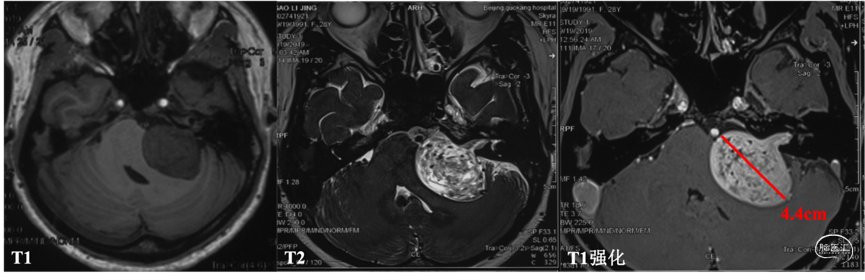

头颅MRI

诊断